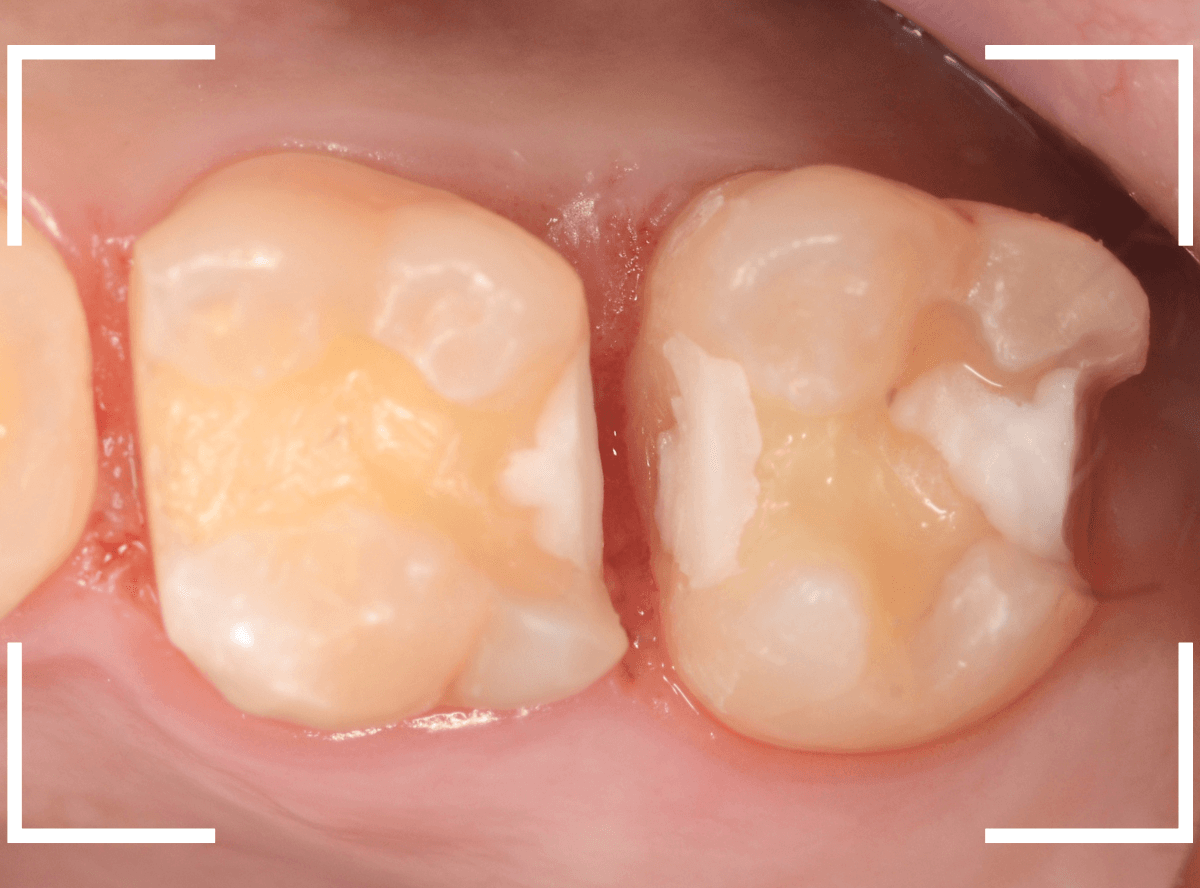

Case.26 4歯連続したセラミック・インレー

4本連続して歯と歯の間の虫歯を治療した患者さんのケースです。

虫歯を再発させないためには、歯と歯のすき間を物がつまらないよう、精密に再製する必要があります。

患者さんのご希望により、セラミック・インレーで修復する事になりました。

模型上で歯と歯のすき間を精密に再現・調整できるのが、セラミック・インレーの大きな利点です。

歯をトリミングして、型を取ります。

模型上で精密に製作します。

最終setした状態です。

左側の大臼歯2本が、ジルコニア・インレー

右側の小臼歯2本が、E-MAX・インレー

になります。

見た目にほとんど遜色ない仕上がりにできました。

普段あまりしない、4歯連続のインレー治療でしたが、精密に仕上げ・setする事が出来てホッとしました。